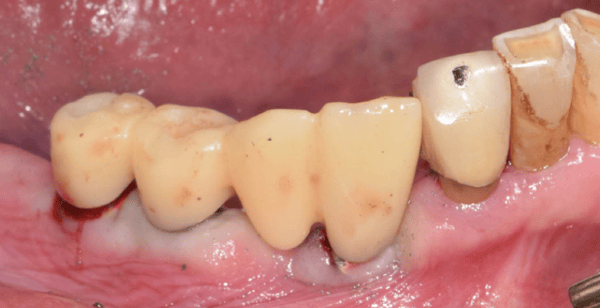

一位長期受牙齒問題困擾的病患走進了診間,他的下顎依賴著一副活動局部假牙維持僅存的咀嚼功能,而右下側的牙橋邊緣已出現繼發性齲齒,多顆牙齒根尖甚至出現病變。對於任何一位經驗豐富的醫師來說,這都是一個棘手的開局。病患渴望植牙,但他提出了一個令許多醫師頭痛的要求:受限於經濟與社交需求,他不願意拔除所有患牙,更不願意在漫長的治療期間經歷無牙的尷尬期。

在數位化介入之前,你可能需要花費大量時間與技工所溝通,反覆進行藻膠印模來確認咬合垂直高度。Jaemin Lee 醫師最初制定了一個穩健的兩階段計畫:先處理左下顎的植牙,保留右側牙橋與 RPD 作為過渡。這是一個合理的打法,透過數位掃描記錄下初始的咬合狀態與軟組織型態,為這場長跑做好了準備。這時,數位檔案就像是一個精準的時空膠囊,完整保存了病患未經破壞前的口腔資訊,這在後續的突發狀況中發揮了決定性的作用。